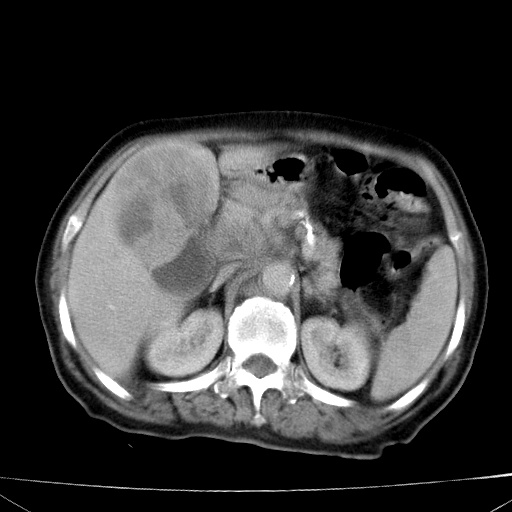

网站人气太旺!昨天的帖子就沉到海底,只好再发贴!ct18338:女 78岁,肝胆病变,已增强,再会诊!原帖链接:http://www.radida.com/bbs/forum.php?mod=viewthread&tid=50032

1)考虑胆囊癌侵犯肝脏并肝门区、腹膜后及右侧膈角后淋巴结转移。2)肝左叶近肝顶部囊肿。3)肝左叶肝内胆管结石。4)左肾近下极囊肿。